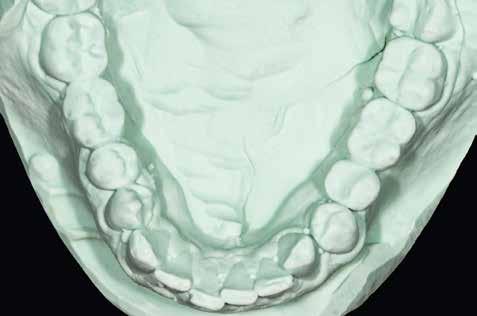

1–2. képek: Kiindulási helyzet.

3. kép: Új teleszkópos fogpótlás az 16, 15, 13, 23 és 27 fogakra.

Teleszkópos munka, élő eset bemutatásával ismertetem, mi az, ami már lehetséges. A munkaasztal-szkenneren kívül bevetésre került a digitális munkafolyamatok során egy intraorális szkenner (IOS) is. A 3D nyomtatású testek gyártása a laboratóriumban LCD- és DLP nyomtatókkal történt. A fémes komponenseket szelektív lézerolvasztásos (SLM) technológiával készíttettük.

Kiindulási helyzet

A páciens látlelete a következő:

• krónikus általános parodontitis

• a 24-től terjedő parodontális fekély

• hatástalan kapcsos felső fogpótlás (1-2. képek)